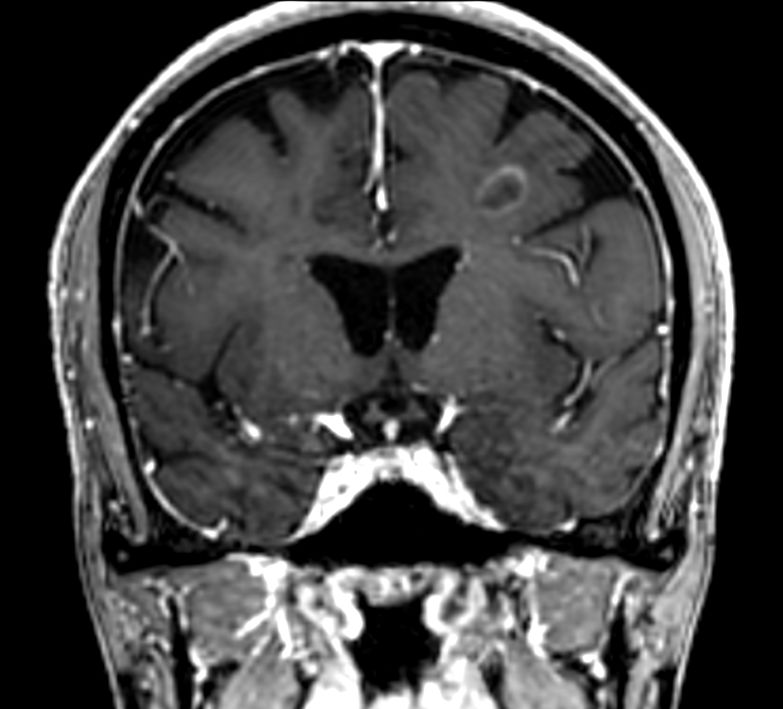

3D T1w FFE +Gado Compressed SENSE

3D T1w FFE (reformat) +Gado Compressed SENSE